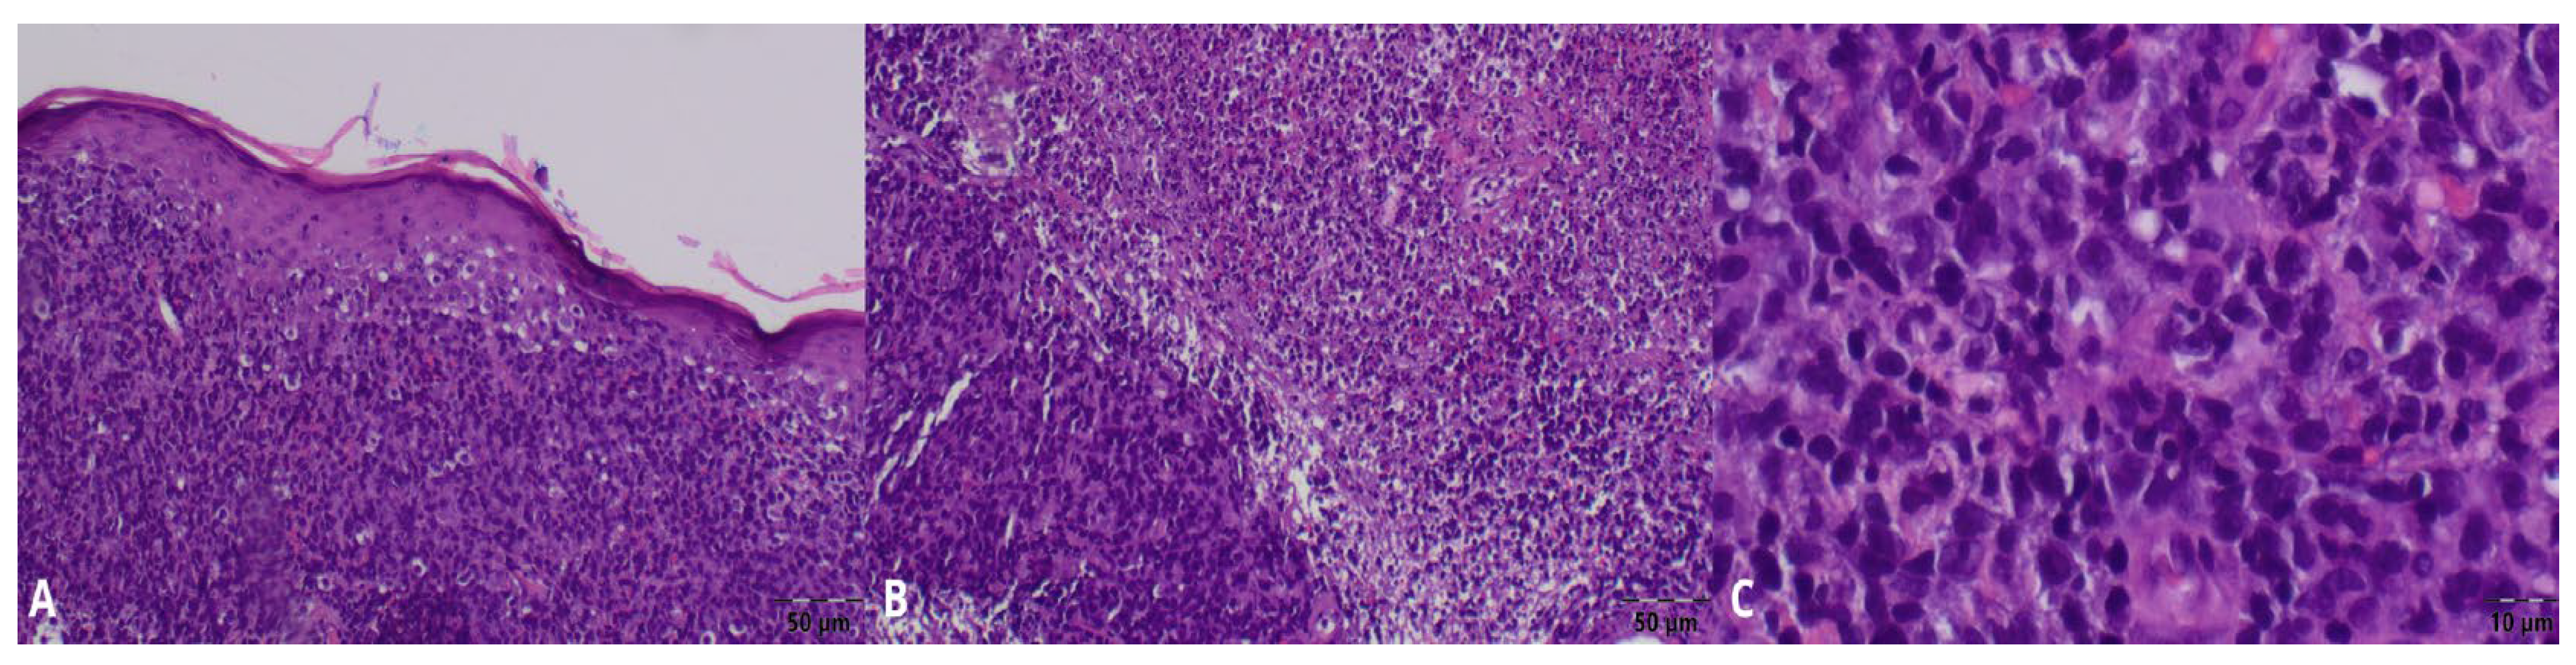

2. Case Presentation